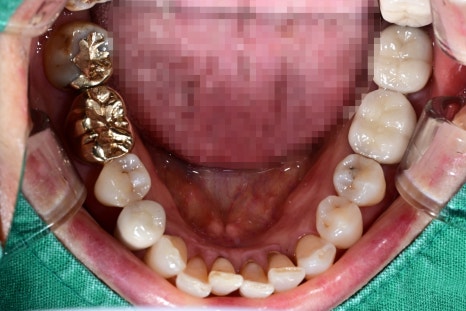

① Removal of the damaged tooth

This is done only when necessary,

and loose teeth or teeth with severe inflammation are removed first.

In the case example, the two upper right molars were extracted

before moving on to the next step.

② Recovery of the jawbone or bone grafting

If the jawbone is weak, it may be difficult for the implant to be firmly fixed,

so a bone supplementation process may be needed.

This is a standard procedure to improve implant stability.

③ Implant placement (screw insertion)

This is performed under local anesthesia and finishes in a relatively short time.

Patients often say, “It ended faster than I expected.”

In this case as well, the surgery to place implants in the positions of the two molars

was completed stably.